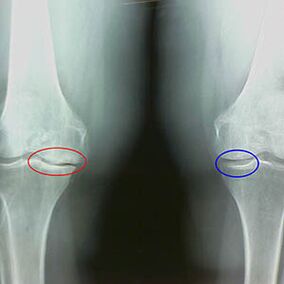

Caracteristici timpurii X -RAY ale celei de -a doua etape a artrozei genunchiului:

- marginile ascuțite ale tuberculilor inter -crib pe tibie, unde este atașat ligamentul în formă de încrucișare;

- îngustarea decalajului articulației pe partea medială;

- Marginile ascuțite ale condililor oaselor pe laturile mediale, mai rar în lateral - în funcție de dezvoltarea valgusului sau a deformării articulare variate.

Pentru a doua etapă din Larsen Îngustarea decalajului articulației cu mai mult de 50% este caracteristică, dar acest lucru poate fi verificat doar în dinamică sau în comparație cu o articulație spre deosebire.

Radiografia arată prezența osteofitelor, o modificare a spațiului dintre oasele femurale și tibie, ceea ce indică pierderea cartilajului la genunchi. Uneori, razele X a articulațiilor genunchiului prezintă semne semnificative de uzură a cartilajului, dar pacienții nu au dureri semnificative.Dimpotrivă, artroza primei etape poate perturba funcția genunchiului, întrucât cauza durerii este mușchii hipotonici.